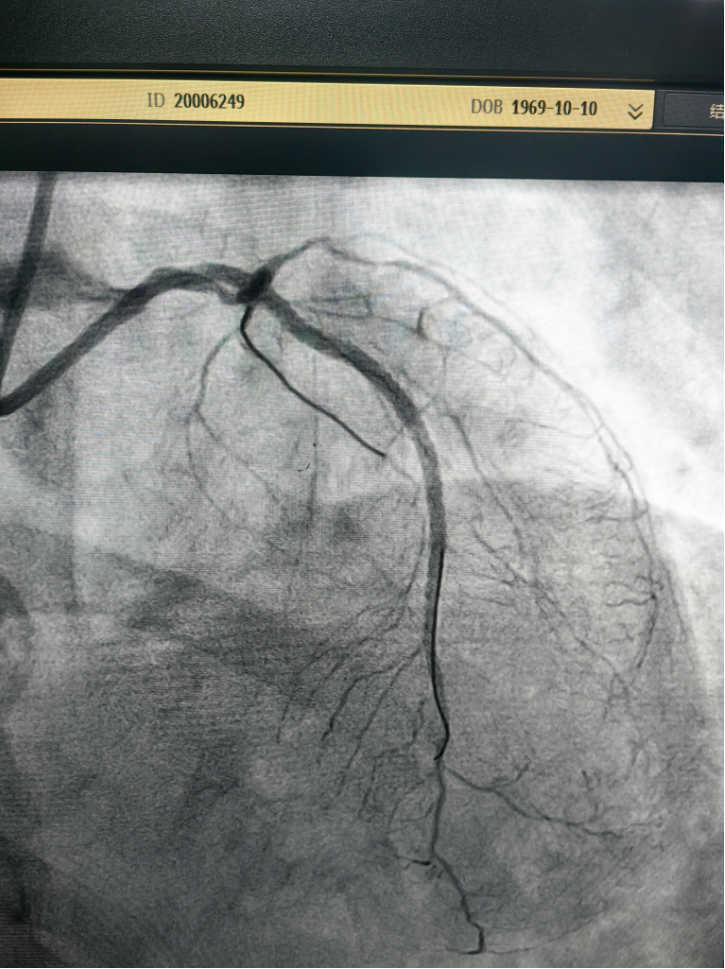

4月21日,在心血管内科主任王景峰教授的指导下,在花都院区DSA(数字减影血管造影)介入平台的配合以及IABP(主动脉内球囊反搏)的辅助下,林茂欢副主任医师带领曹正宇助理研究员和王春红主管护师成功抢救一例急性心梗合并急性左心衰的重症患者,顺利完成急诊介入手术。

据悉,患者为55岁女性,因血糖控制不佳就诊。住院期间,她突发胸痛,诊断为急性非ST段抬高型心肌梗死,其冠脉三支血管严重病变,其中一支血管完全闭塞,术中出现急性左心衰发作,病情危急。团队迅速启动抢救预案,在药物抢救的基础上及时置入IABP辅助循环治疗,经过半个小时的积极抢救,患者转危为安,生命体征稳定。

术前(左一、左二)、术后(右一)